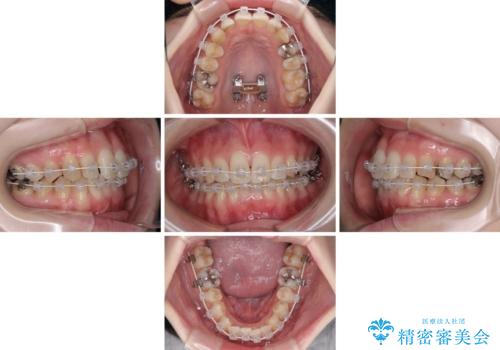

- 急速拡大装置・審美装置

急速拡大装置により上顎骨を側方に拡大し、ワイヤー装置により歯列を整えることとしました。